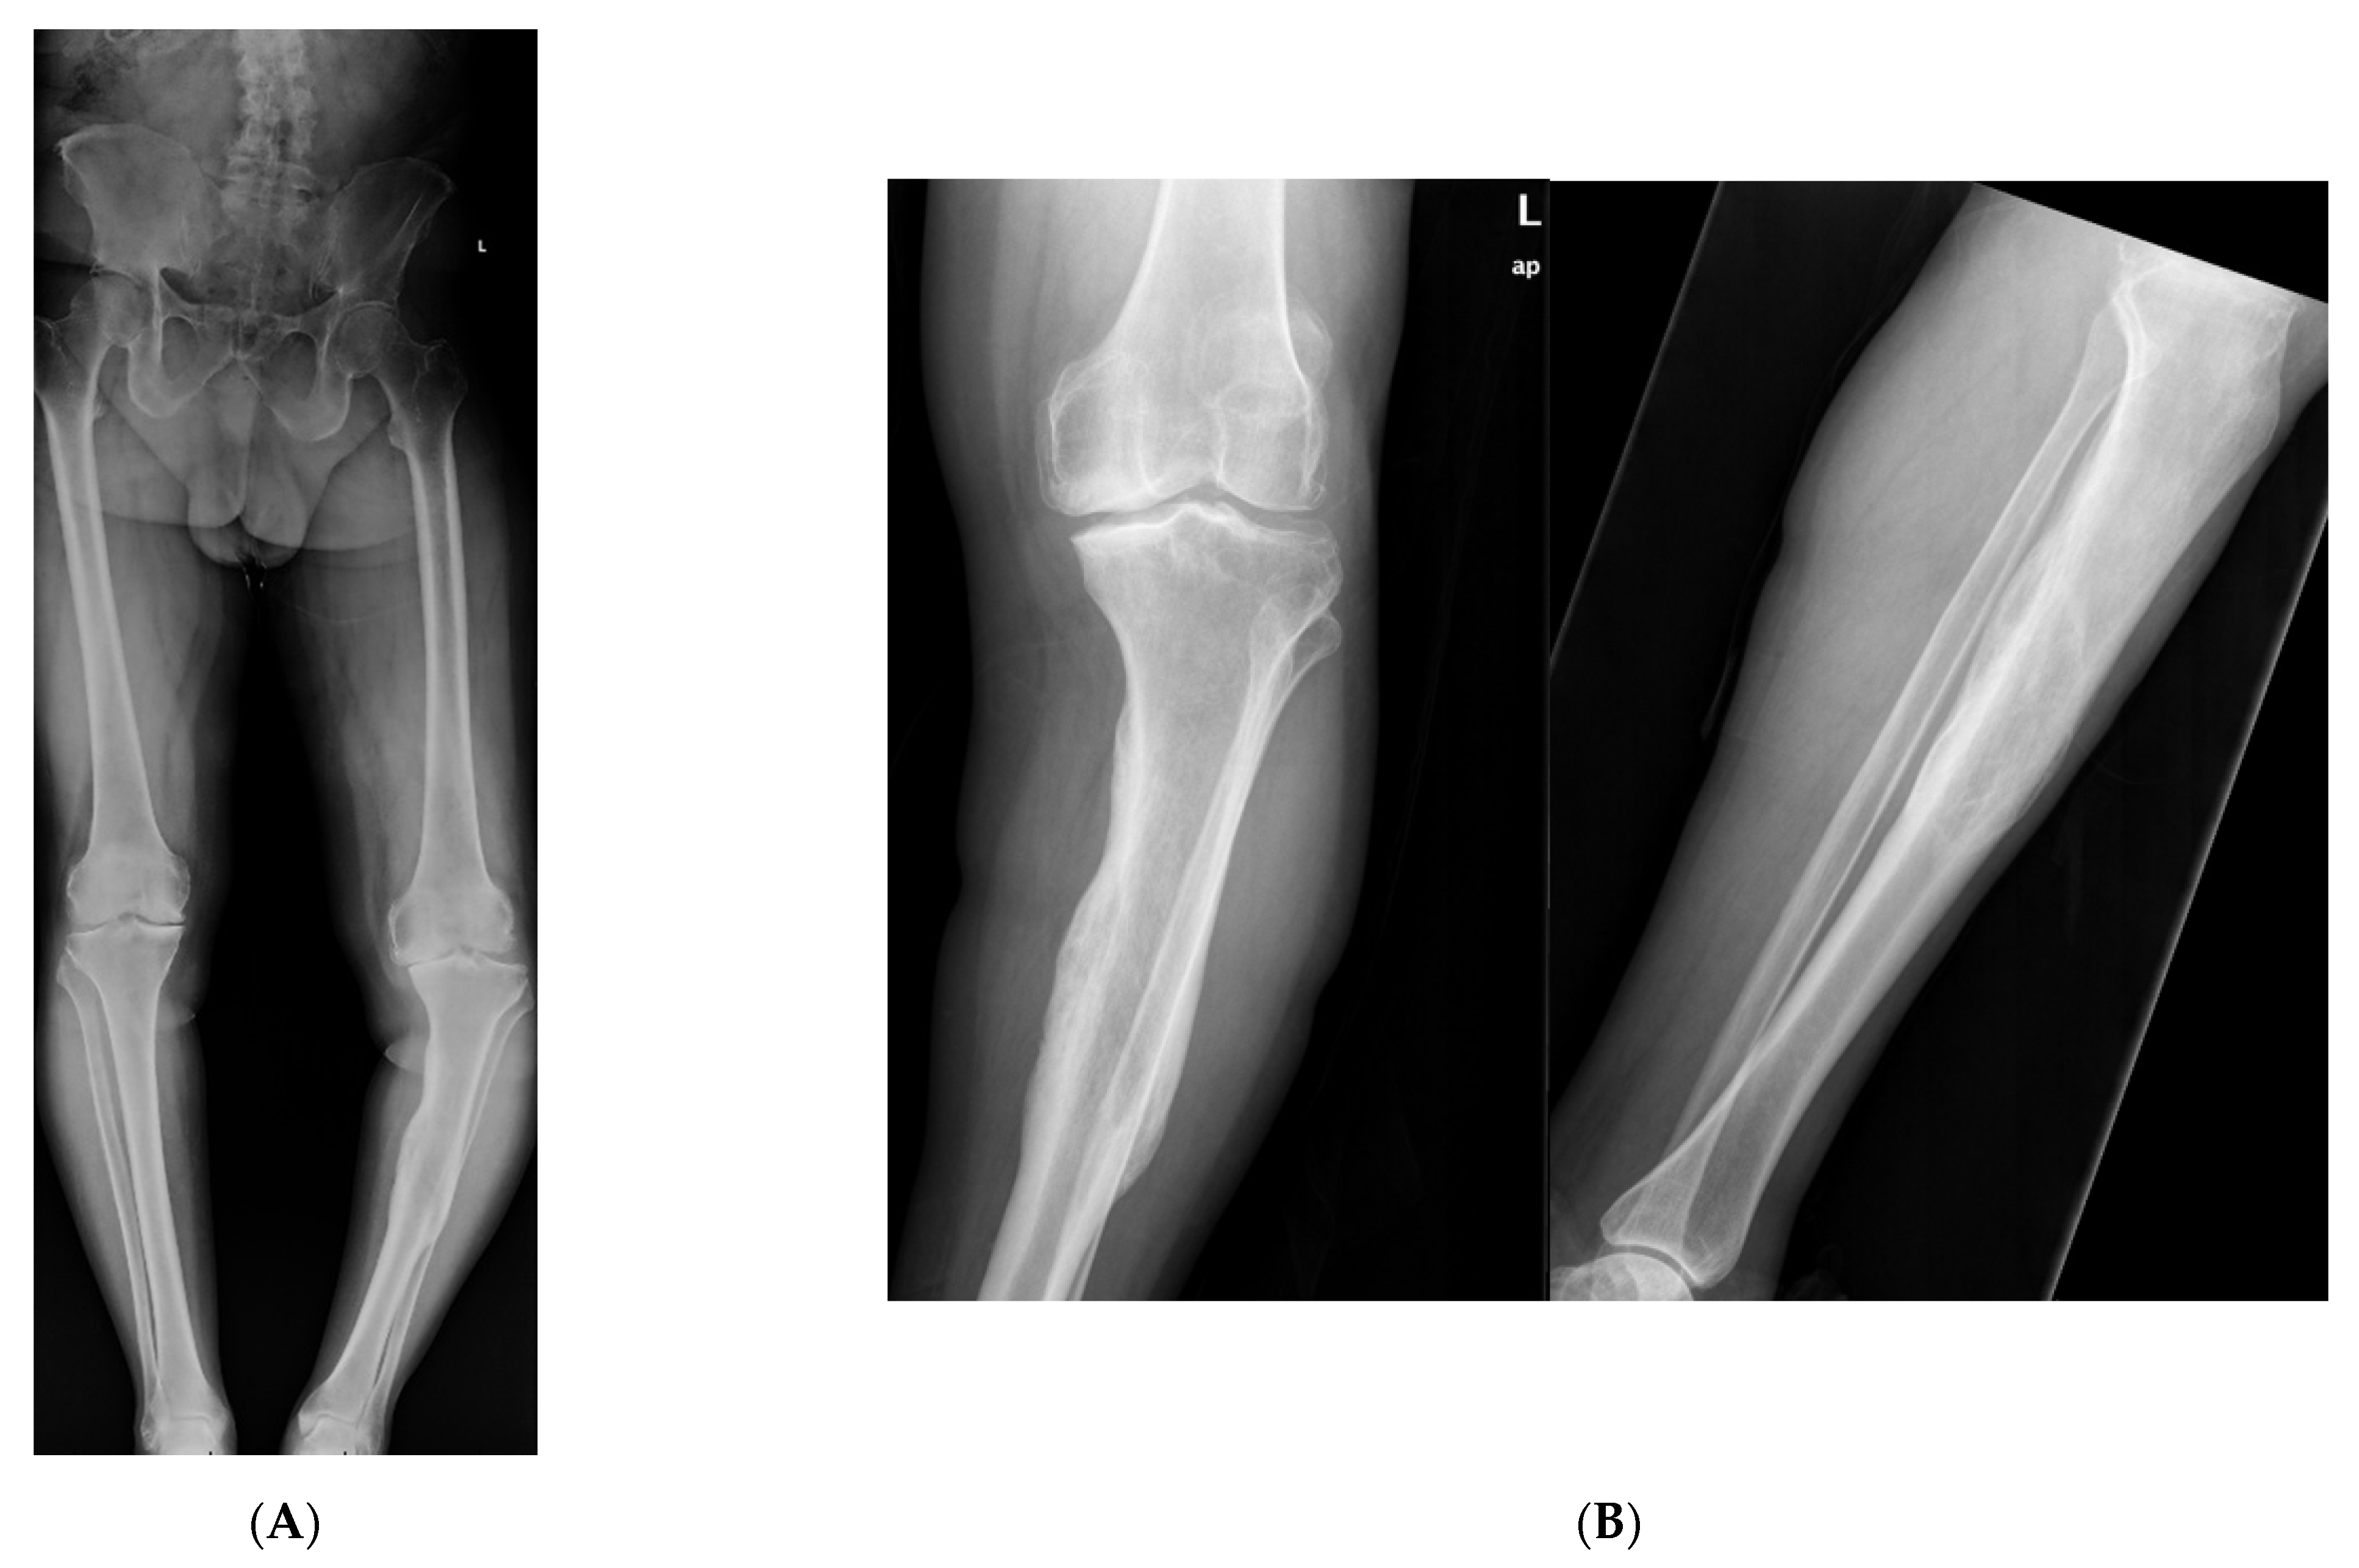

An elderly male presented to clinic with an obvious deformity to his left leg with a chronic history of left knee and ankle pain. He sustained a fracture of the proximal third of the tibial diaphysis approximately 7 years prior that was managed non-operatively in a long leg cast. He subsequently developed a posttraumatic tibial varus deformity with severe tricompartmental knee arthritis. His primary complaints were abnormal gait pattern, and severe functional knee pain. Physical examination was significant for tibial shortening, genu varus, and internal tibial torsion. Full-length radiographs revealed medial mechanical axis deviation. His medial proximal tibial angle measured 78° and the apex of angulation at center of rotation of angulation measured 14°. Total knee arthroplasty was not an option secondary to his severe extra-articular deformity that could predispose to early implant failure. Thus, deformity correction was undertaken with a clamshell osteotomy (Figure 4). A posteromedial approach was used to expose the malunited segment. In follow up care, wound dehiscence of the posteromedial approach was noted, requiring local wound care and oral antibiotics. Eventually, he healed his osteotomy uneventfully, and was able to obtain a total knee arthroplasty.

Figure 4. (A): Full length standing radiographs illustrating a left tibia diaphyseal malunion. (B): AP and lateral of tibia showing a diaphyseal malunion. (C): Intraoperative fluoro demonstrating bicortical drill holes parallel to medial face of the tibia. This is prior to the utilization of the osteotome and the perpendicular saw cut. Remember to remove retractors prior to the reaming process. (D): Intraoperative fluoro illustrating the clamshell osteotomy. Notice secondary fracture line propagated during the osteotomy (red arrow). (E): The reamer was pushed pass the osteotomy zone during the reaming process. This is to prevent iatrogenic injury to neurovascular structures. (F): AP and lateral fluoroscopic images demonstrating improved alignment after clamshell osteotomy and implantation of intramedullary nail. Poller screws may be required to assist with reduction. However, the poller screw in this scenario was inserted for definitive fixation to prevent any endosteal motion of intramedullary nail. (G): AP and lateral XR demonstrating osseous union at 3 month follow up.